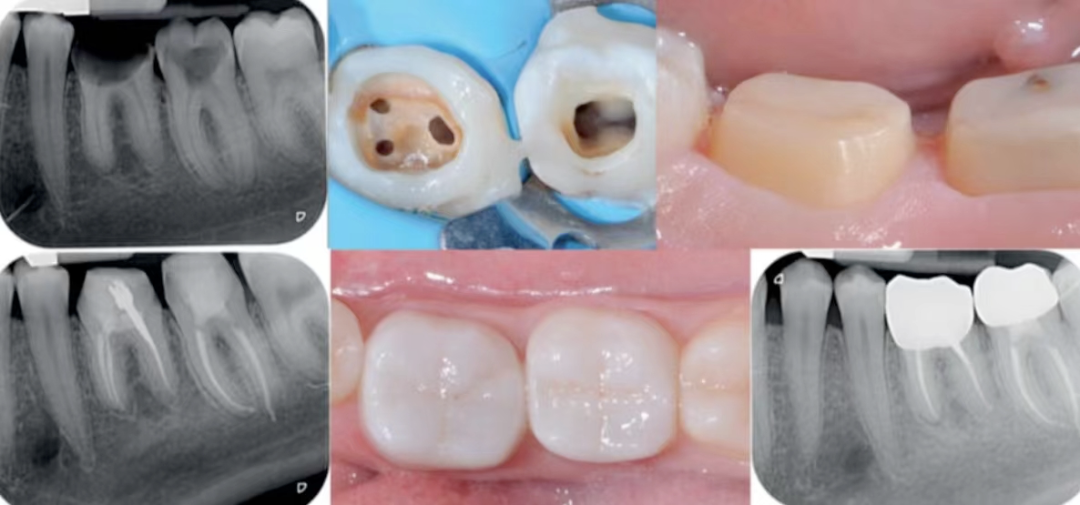

磨牙龈壁提升高嵌体修复一例

术前照片

主诉:右下后牙充填物脱落3天。

现病史:患者自诉右下后牙五年前在外院充填,3天前充填物脱落,否认自觉症状,由于食物嵌塞,影响进食,遂来我院就诊。

既往史:体健。

口腔检查:46远中邻面可见深大龋洞,窝洞内可见黑褐色腐质,质软,至牙本质深层。冷诊无明显反应。叩痛(-),牙髓活力测试正常。

辅助检查:46根尖未见异常。

诊断:46深龋

治疗方案:46嵌体修复

局部麻醉下进行去除腐质,可见远中邻面边缘位于龈下。由于近髓,剩余核心区域腐质橡皮障隔离后再进行去除。

橡皮障隔离患牙,去净腐质,然后进行详细的生物力学分析,远中舌尖无牙本质支撑,需要牙尖覆盖,降低1.5mm左右,远中颊尖厚度足够。近中邻面边缘嵴完整,远中邻面边缘需要进行CMR。

圈型成型片完美隔离,喷砂牙本质表面,将牙本质表面进行37%磷酸酸蚀15秒,轻轻风干5秒后涂布粘接系统,进行IDS。

进行IDS,远中邻面进行CMR

进行牙体预备,抛光牙面,保持内线角圆钝,检查功能尖和洞缘的距离。

修复体制作完成,检查边缘密合性,邻面接触。

氢氟酸处理修复体,超声震荡后,涂布硅烷偶联剂静置。

橡皮障隔离四个单位,清洁,抛光牙面。

试戴修复体,检查修复体就位情况,边缘密合性。

试戴颊侧观

27微米氧化铝进行牙面喷砂

颊侧观,可见粘接面平坦。

进行磷酸酸蚀。

舌侧观

树脂水门汀粘接,去除多余粘接材料

各个面光固化60秒。

粘接后即刻

粘接后颊侧观,可见边缘密合。

邻面接触尚可

进行牙面抛光。

粘接后口内即刻。

咬合检测

口内颊侧观

术前术后对比